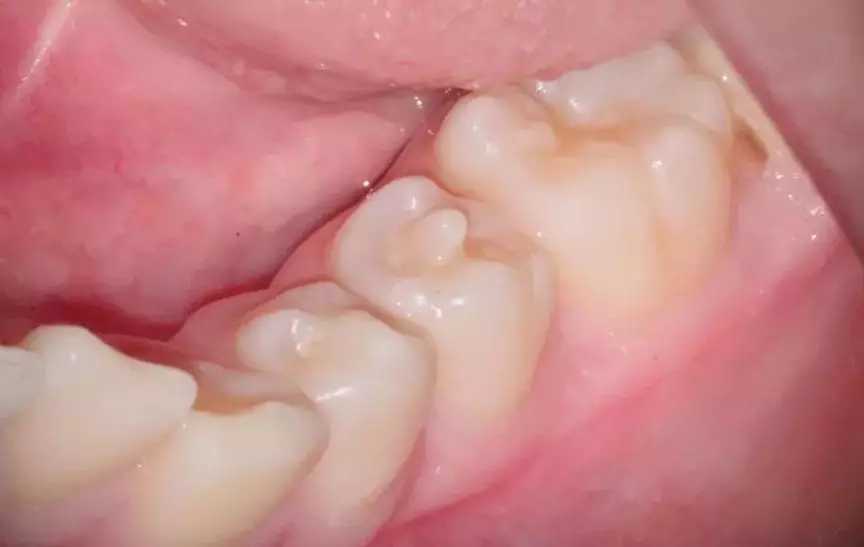

对侧牙齿中央有个小尖

这个“小尖”被称为畸形中央尖,多见于下颌前磨牙,尤以第二前磨牙多见.一般位于合面中央,呈圆锥形突起.一般约2~3mm,临床上,畸形中央尖通常因磨损而变圆钝或因咀嚼硬物而折断。

所以,在小朋友牙齿替换过程中,家长应注意检查新萌前磨牙上是否有异常凸起的牙尖,一旦发现,应避免用患牙咬物以防畸形中央尖折断,并尽快就医,寻求治疗。